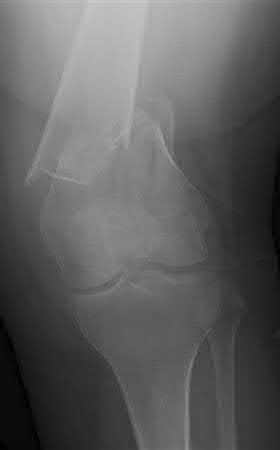

Buttress plating is most appropriate in which of the following clinical situations?

Buttress plating is appropriate for a Shatzker Type I (see illustration C), as it can prevent collapse and axial deformity from shear or bending forces.

Figure B demonstrates an isolated medial femoral condyle fracture. Lateral locked plating is not an appropriate technique for this fracture.

The fracture shown in Figure B is an AO B type (partial articular fracture). This fracture is best treated with open reduction internal fixation through a medial approach, with lag screw and buttress plate fixation.

Figures A, C, D and E show supracondylar distal femur fractures that can be treated with ORIF with a fixed-angle device such as lateral locked plating.